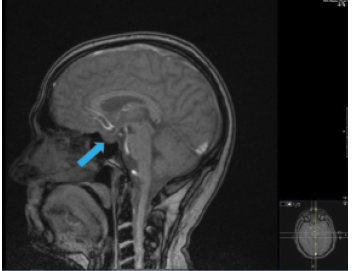

I thought that the changes in this patient’s visual acuity could be attributed to bilateral cataracts. The inferior nasal step in his left eye appeared to be localized to the RNFL. The other visual field changes respected the horizontal meridian, however, and seemed out of proportion to the RNFL damage. I ordered an MRI of the brain with and without contrast and subsequently referred this patient to neurosurgery for treatment based on findings of a pituitary mass (Figures 3–5). He subsequently underwent resection of the mass (Figure 6).

Figure 3. T1-weighted MRI scan, coronal section, with contrast. Blue arrow indicates the growing pituitary mass.

Figure 4. T1-weighted MRI scan, coronal section, with contrast. Blue arrow indicates the growing pituitary mass. Labeled elongated blue arrow indicates the optic chiasm.